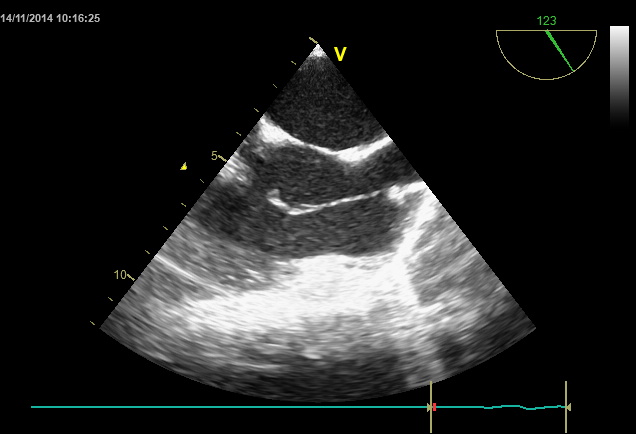

Palpitations !

Mme XX âgée de 40 ans, sans ATCD particuliers, symptomatique de palpitations gênantes.

L’ECG s’inscrit en RS, pas de trouble de conduction pas de trouble de repolarisation.

L’holter rythmique n’a pas objectivé de trouble rythmique.a